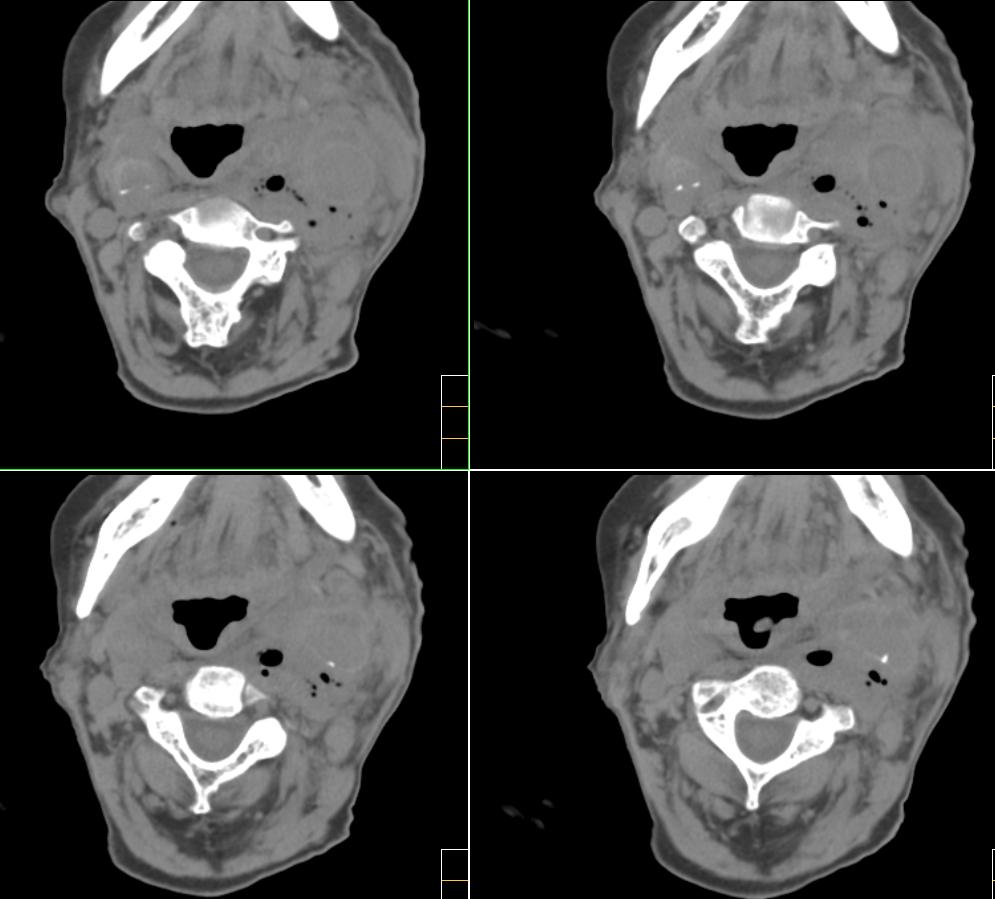

标题: CT4272:求助!颈部血管瘤破裂?

f、72y,左侧颈部发现包块及疼痛1周,彩超提示颈部血管破裂?

考虑血管破裂没什么问题,但颈部这么多积气哪来的?有外伤吗?或颈部脓肿腐蚀血管?

考虑1颈部脓肿侵蚀血管致血管瘤形成。2甲状腺左叶占位。

考虑颈部脓肿,并侵蚀血管后形成动脉瘤的可能性大;左侧甲状腺肿瘤.

软组织内积气来源为颈部产气菌感染所致.

左颈部血管增粗,周围软组织肿胀模糊,内有蜂窝状积气影,左侧甲状腺增大,气管受压右移,气管软骨环未受侵。结合病史较短考虑:左颈部脓肿破裂并血管瘤形成,左甲状腺瘤。